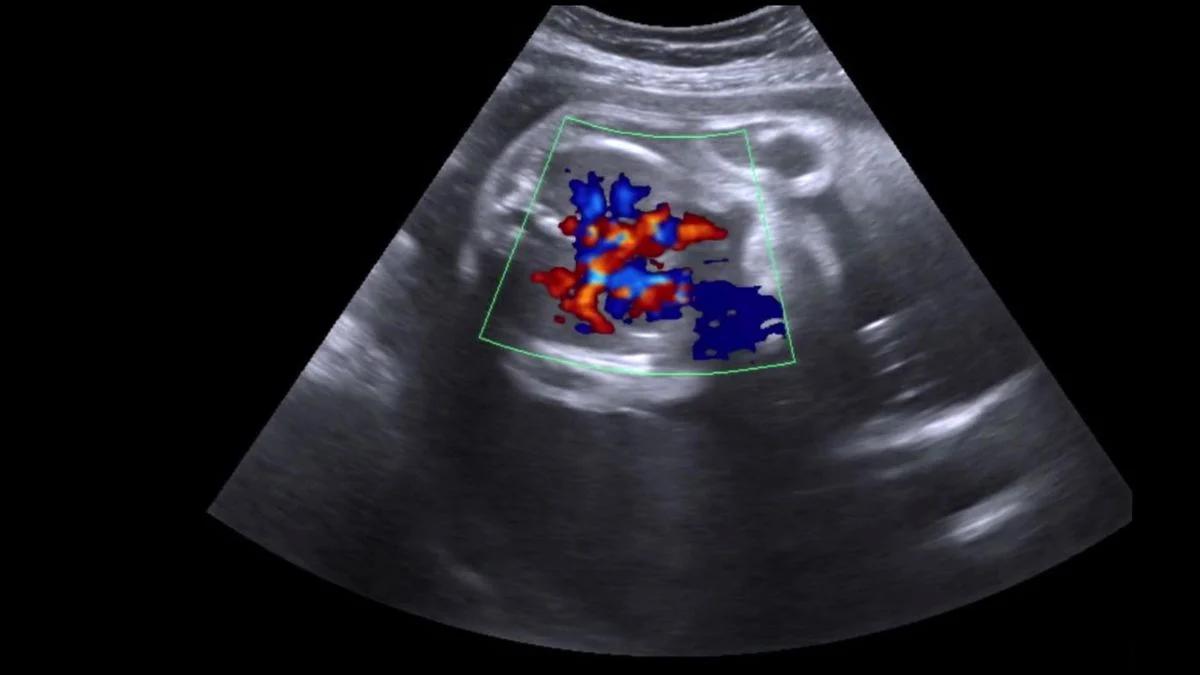

Ein Doppler-Ultraschallgerät ist ein handliches Gerät, das mithilfe von Schallwellen die Herzfrequenz des ungeborenen Kindes messen kann. Es funktioniert nach dem Prinzip des Doppler-Effekts, bei dem sich die Frequenz von Schallwellen verändert, wenn sich die Schallquelle oder der Empfänger bewegt.

Durch die Anwendung von Ultraschallwellen auf den Bauch der Schwangeren kann das Gerät die Bewegung des kindlichen Herzens erkennen und die Herzfrequenz messen. Die Ergebnisse werden in der Regel auf einem kleinen Display angezeigt.